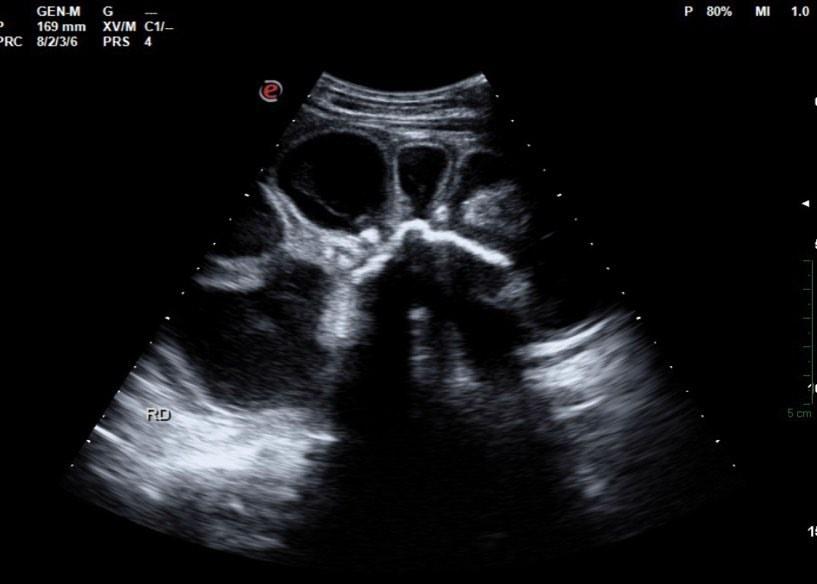

A simple way to grade hydronephrosis is by severity, mild to severe.

Mild

Pelvic fullness with no calyceal dilatation

Moderate

Greater expansion of the renal pelvis and involvement of the calyces

Severe

Further dilatation of the renal collecting system with cortical thinning

It’s good practice to always place color doppler on mild hydronephrosis or extra-renal pelves to distinguish a true fluid collection form a prominent renal vein.